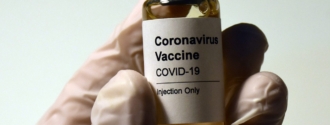

As many countries ramp up efforts to stop the novel coronavirus from spreading and roll out mass COVID-19 vaccination programs, we’re reminded that every minute counts when someone’s health is on the line.